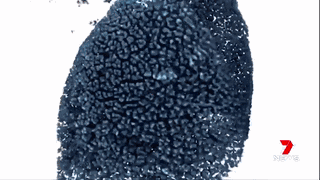

澳洲的科學(xué)家們通過運(yùn)用納米技術(shù),將“基因沉默”(gene silencing)藥物運(yùn)送至腫瘤細(xì)胞中來治療胰腺癌。

藥物已經(jīng)在擁有和人類相仿的瘢痕組織的小鼠身上進(jìn)行試驗(yàn),并獲得成功。